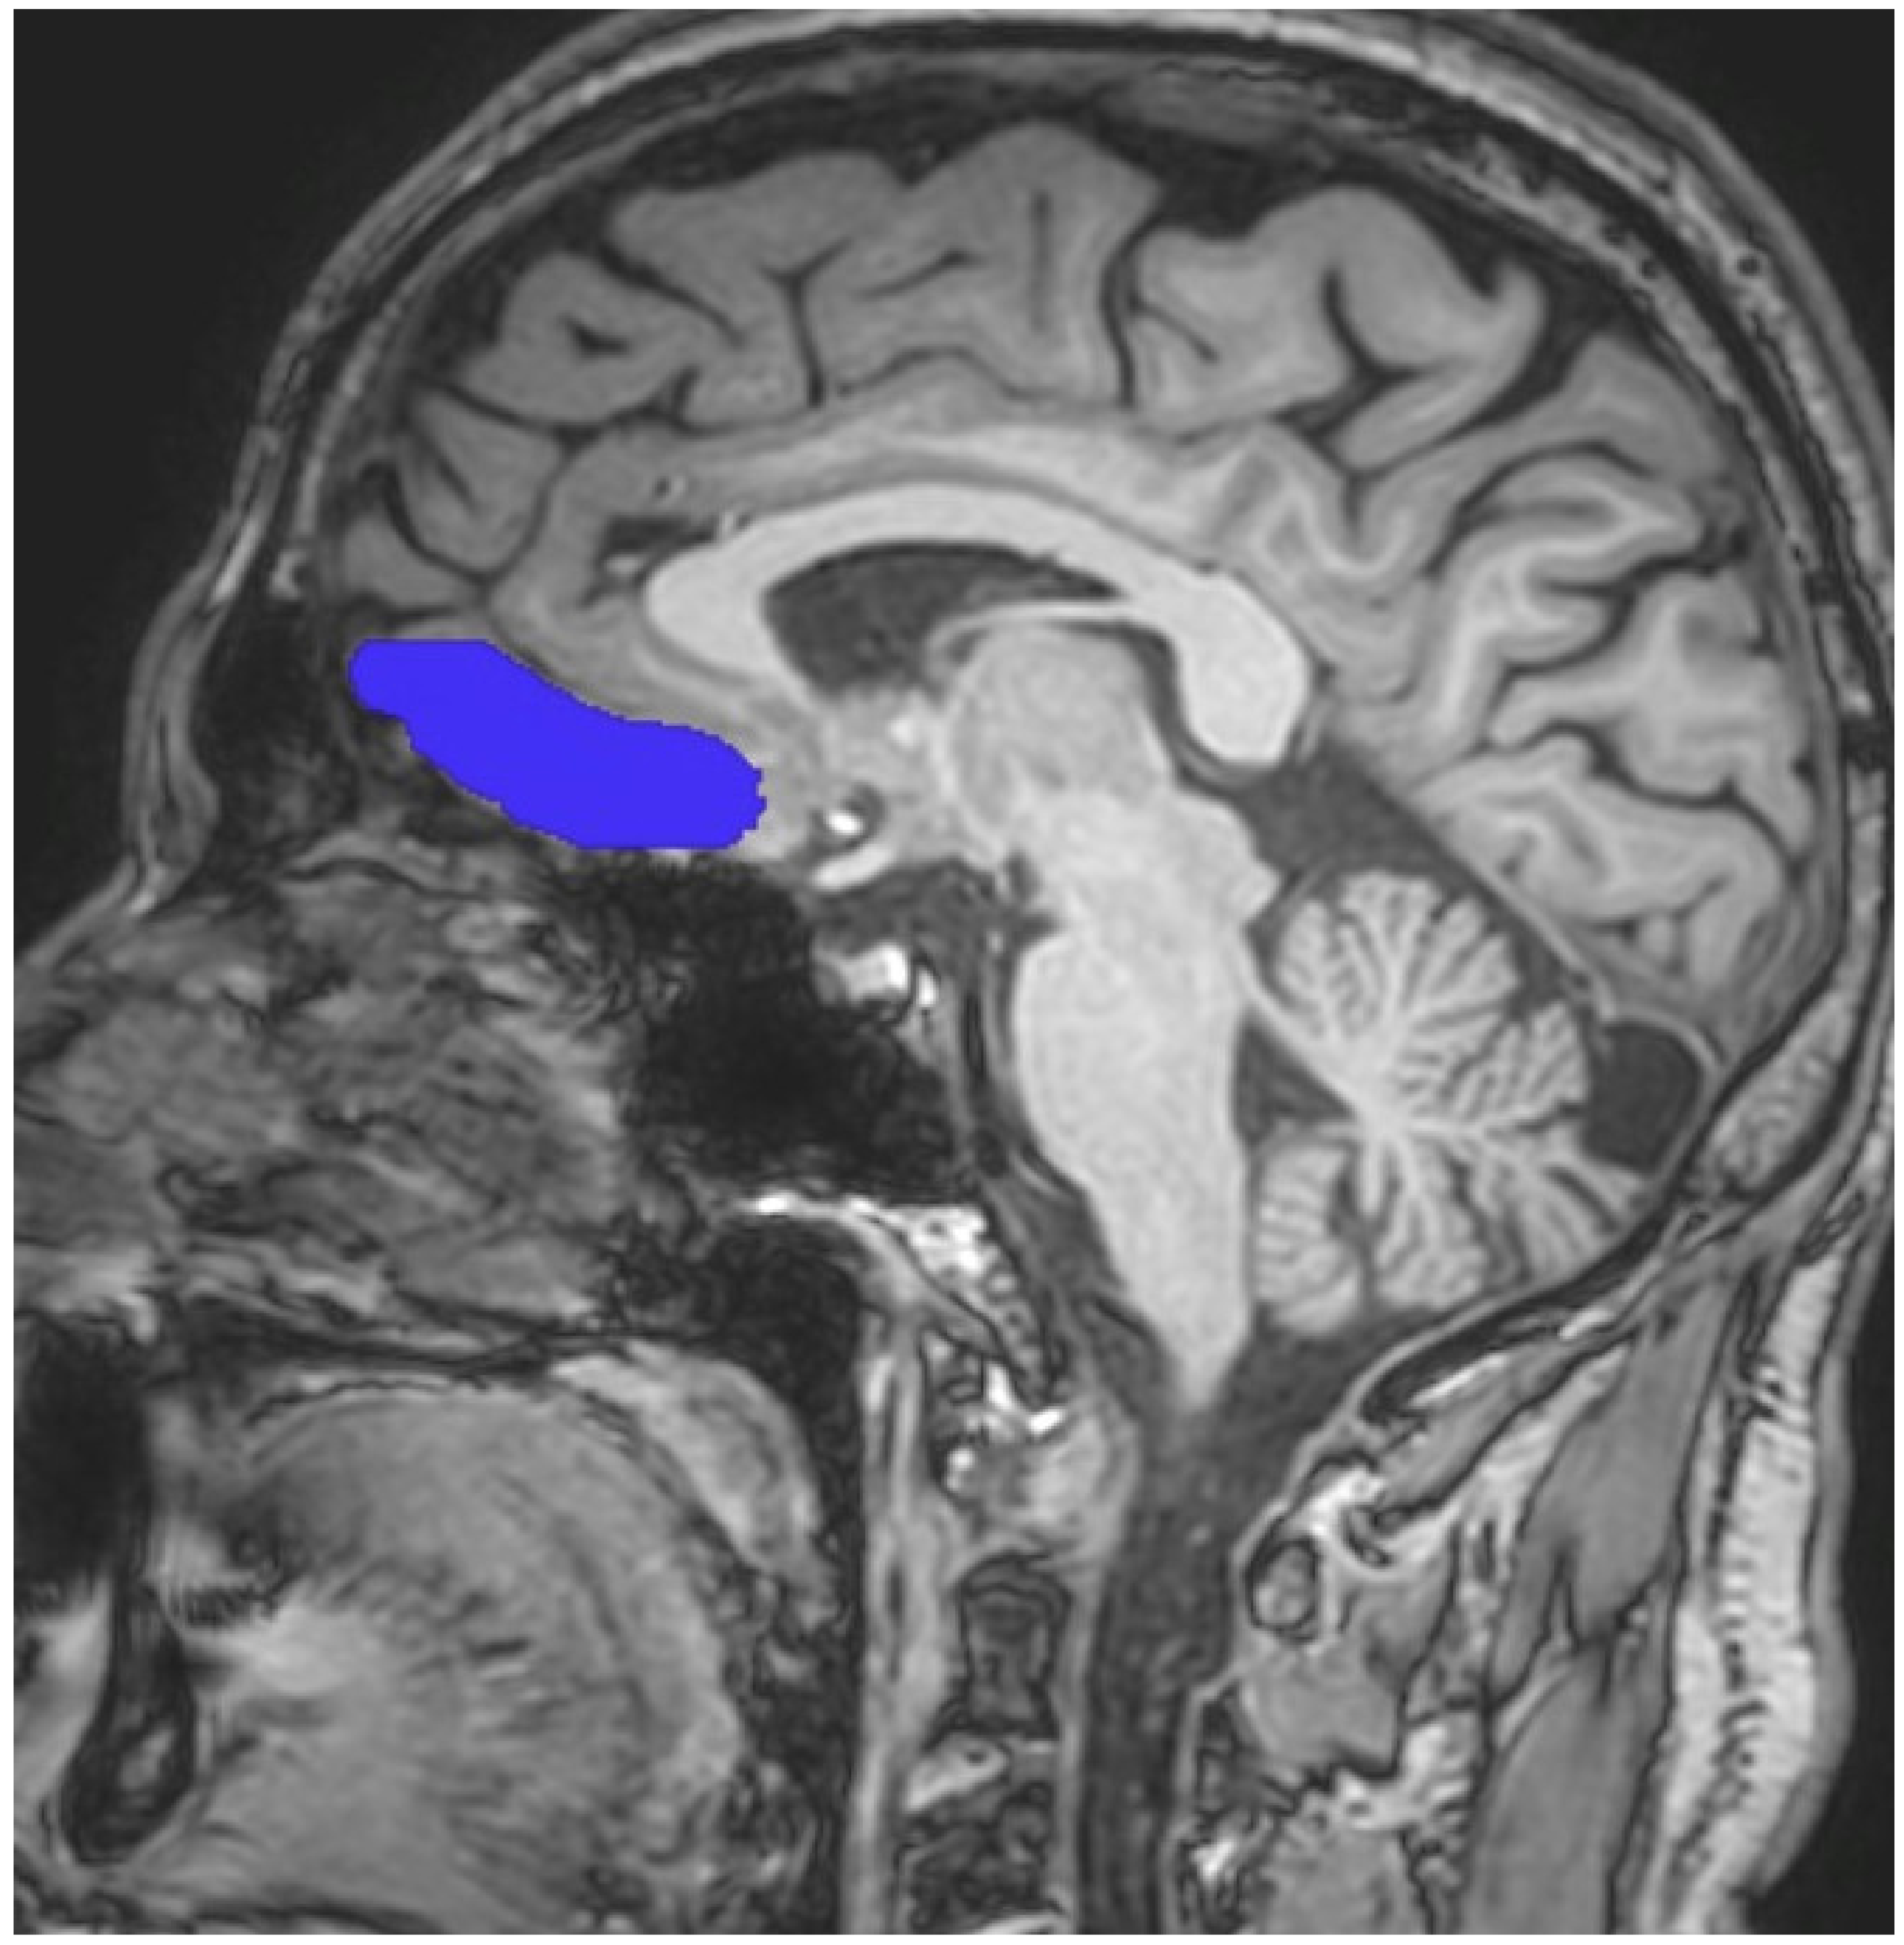

2.2. Magnetic Resonance Imaging (MRI) Procedure

- Yuh, W.T.C.; Afifi, A.K.; Tali, E.T. MRI of Head & Neck Anatomy; Churchill Livingstone: London, UK, 1994; ISBN 0443088926. [Google Scholar]

- Jackson, G.D.; Duncan, J.S. MRI Neuroanatomy: A New Angle on the Brain; WB Saunders Company: New York, NY, USA; Churchill Livingstone: London, UK, 1996; ISBN 0443045437. [Google Scholar]

- Patel, V.H.; Friedman, L. MRI of the Brainnormal Anatomy and Normal Variants; W.B. Saunders Co., Ltd.: Philadelphia, PA, USA, 1997; ISBN 072166945X. [Google Scholar]